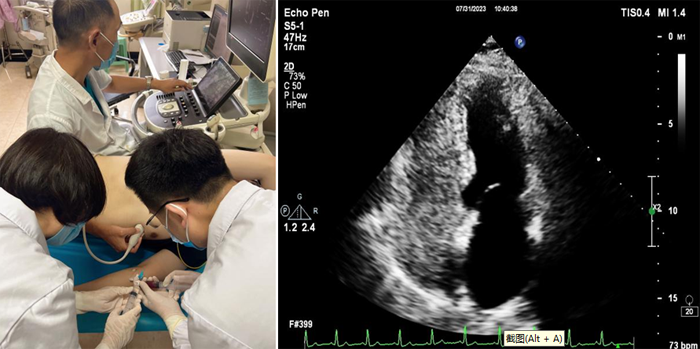

近日,我院超聲科聯(lián)合介入室、CCU 及神經(jīng)內(nèi)科成功完成首例經(jīng)胸右心聲學(xué)造影檢查。該項(xiàng)檢查填補(bǔ)了我院在超聲造影檢查的一項(xiàng)空白,該技術(shù)在魯西南地區(qū)屬領(lǐng)先水平,為我院心腦血管疾病的診斷又添新技術(shù)。

右心聲學(xué)造影又稱發(fā)泡實(shí)驗(yàn),是利用靜脈注射手震微氣泡生理鹽水造影劑,使右心系統(tǒng)顯影,造影劑氣泡直徑>10微米,平均約15微米,正常情形下微氣泡不能通過(guò)肺毛細(xì)血管網(wǎng),從靜脈血管輸入后只出現(xiàn)在右心,不進(jìn)入左心系統(tǒng)。由于微泡與血液存在明顯聲阻抗差,即使個(gè)別微泡(低速微量血流)也能清晰顯示,如果在患者的左心房或者左心室看到有微氣泡,則提示可能是從異常的通路由右心腔到達(dá)左心腔,即常說(shuō)的右向左分流。同時(shí),檢查中還可以根據(jù)微氣泡在左心腔室出現(xiàn)的時(shí)間早晚,初步判斷異常是出現(xiàn)在心房心室間隔的缺損,還是出現(xiàn)在心外結(jié)構(gòu)的異常,例如肺動(dòng)靜脈瘺等。

6.右心造影劑制作:被檢者肘靜脈留置靜脈通路。連接三通管,使用一支20ml注射器抽取8ml生理鹽水后再回抽1ml受檢者自體血液,連接三通管的一端;再用一支20ml注射器抽取1ml空氣連接三通管的另一端;然后將兩支注射器通過(guò)三通管快速互相推送震蕩20次,使空氣、生理鹽水、血液三者均勻混合。

7.操作時(shí),造影劑以彈丸方式快速注入。留存動(dòng)態(tài)圖,靜息狀態(tài)操作1次,Valsalva動(dòng)作后操作 1次至2次。

8.選取四腔心切面,分別觀察靜息狀態(tài)及Valsalva動(dòng)作后左心腔內(nèi)微泡顯影情況。